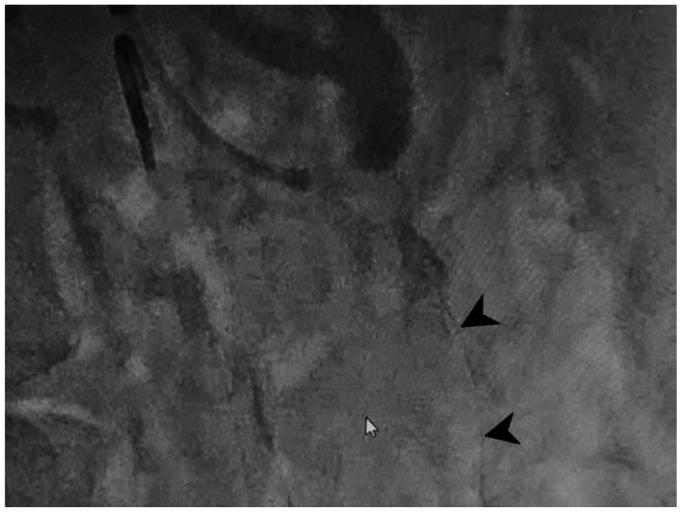

The celiacomesenteric trunk (CMT) is a rare anatomical variant where the celiac axis and superior mesenteric artery share a common origin. Despite its rarity, CMT has significant implications across various medical fields, particularly in surgical planning and interventional procedures. We report a case of chronic mesenteric ischemia owing to atherosclerotic stenosis at the CMT bifurcation, necessitating a complex interventional approach. Kissing covered stent angioplasty was successfully performed, resulting in revascularization, symptom resolution, and no restenosis at 1-year follow-up. This report highlights the feasibility and effectiveness of the kissing stent technique in managing complex CMT bifurcation obstructions in patients with chronic mesenteric ischemia.

腹腔肠系膜干(CMT)是一种罕见的解剖变异,即腹腔干和肠系膜上动脉有共同的起源。尽管CMT罕见,但它在各个医学领域都有重要意义,尤其是在手术规划和介入操作方面。我们报告一例因CMT分叉处动脉粥样硬化狭窄导致的慢性肠系膜缺血病例,需要采用复杂的介入方法。成功实施了吻合法覆膜支架血管成形术,实现了血管再通、症状缓解,且在1年随访时无再狭窄。本报告强调了吻合法支架技术在处理慢性肠系膜缺血患者复杂CMT分叉处梗阻方面的可行性和有效性。